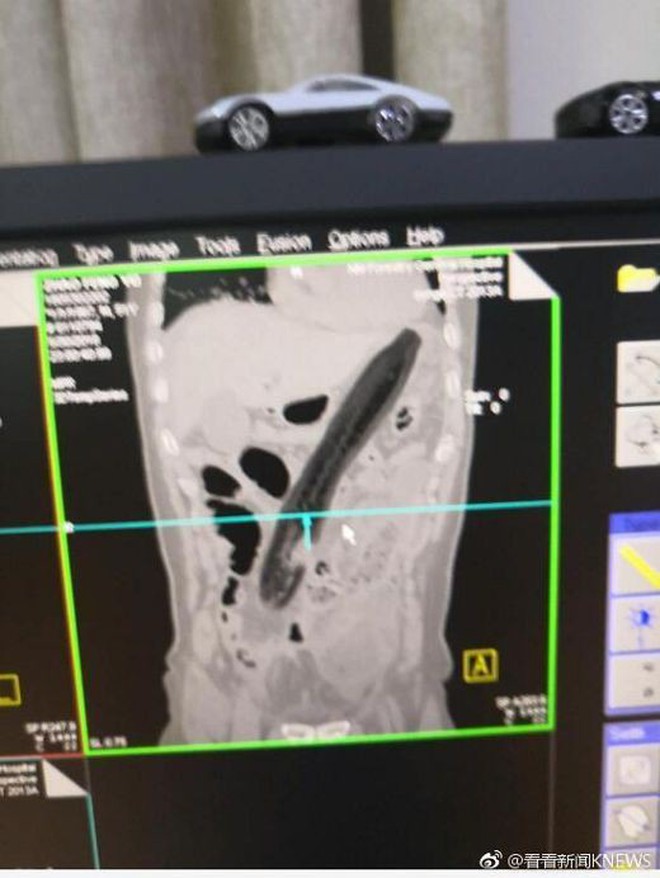

Hình ảnh chụp ích quang vị trí quả cả tím trong cơ thể người đàn ông.

Tại bệnh viện, hình ảnh X-quang cho thấy quả cà tím khổng lồ được đẩy vào mông người đàn ông đã gây ảnh hưởng đến phổi. Các bác sĩ tại bệnh viện phải tìm cách để rút dị vật ra ngoài. Tại đây, người ta đo được quả cà tím dài đến 30cm.

Quả cà tím dài 30 cm.